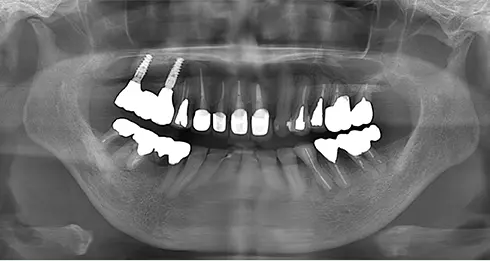

| 年齢/性別 | 60代女性 |

| 主訴 | 前歯が前に出てきた |

| 治療内容 | 全体的に歯周病やむし歯、根の治療(ヘミセクション)を実施。右上の歯にはサイナスリフト術を行い、骨の回復を待った後、半年後に2本のインプラントを埋入しました。 |

| 治療期間 | 9か月 |

| 費用 | 1,298,000円税込 |

| リスク・副作用 | 炎症反応によって術後に腫れや副鼻腔炎が生じることがあります。その程度は、手術の範囲や方法によって異なりますが、多くの場合、時間の経過とともに徐々に治まります。

ごく稀に、下顎奥歯の外科手術後に、唇や顎に痺れを感じることがあります。 |